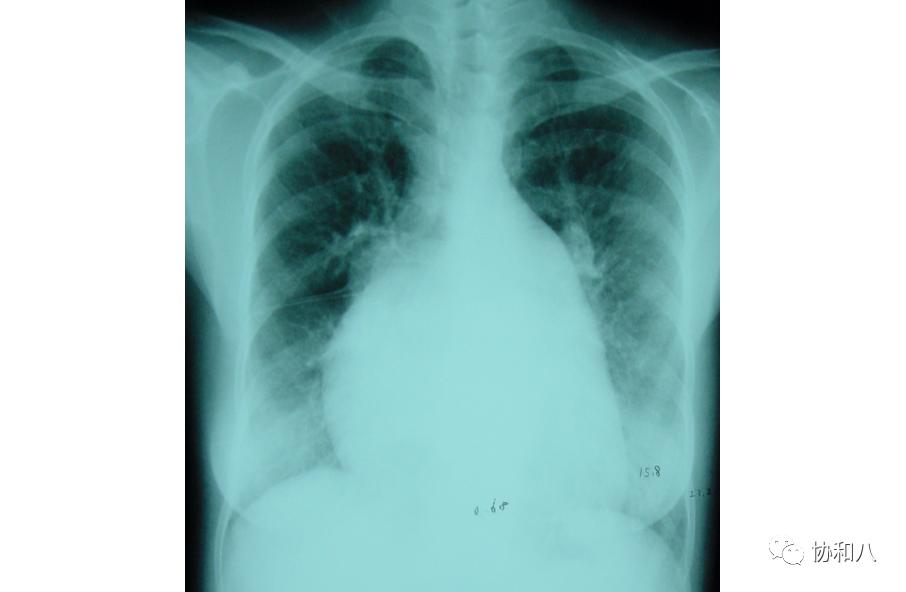

7. 梨形心:

又称“二尖瓣”型心。由于严重的二尖瓣狭窄,左心房及右心室增大,左心房耳部突出,右心房轻度增大。在X线平片上显示为“梨形心”。